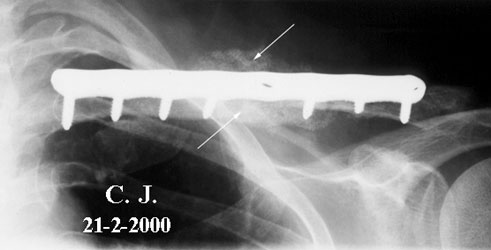

Image n° 2:

four months after surgery

(02 - 21 - 2000)